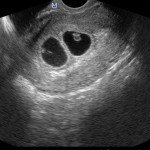

Con l’ecografia transvaginale è possibile vedere dopo circa 3 settimane dal concepimento la camera gestazionale nella cavità uterina. Successivamente è possibile visualizzare l’embrione (3-5 mm.) a circa 6 settimane dall’ultima mestruazione (4 settimane dal concepimento) ed a questo periodo è già visibile l’attività cardiaca fetale Anche i primi dettagli sulla morfologia fetale (polo cefalico, abbozzi degli arti) sono visualizzabili più precocemente con l’ecografia transvaginale, risultando essi visibili intorno a 8-9 settimane.